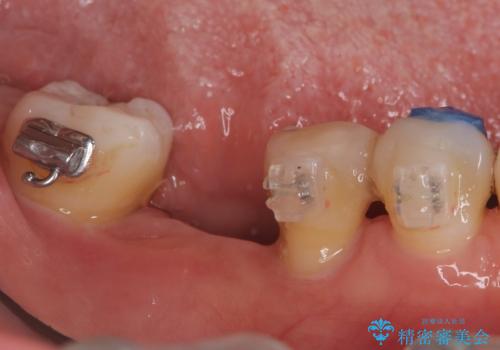

歯周病の原因に咬合干渉が疑われる為、ワイヤーにて固定を行っています。

右下小臼歯は歯周病で大きな骨欠損を認めていました。

できる限り歯が保存できるように治療したいとのことでエムドゲインを用いた再生治療を行っています。